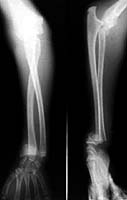

This 14 year old boy presented with closed injury to ipsilateral elbow and wrist.I hope that the pictures are clear (Elbow dislocation, radial neck fracture and distal radial epiphyseal injury).

I would welcome your thoughts on it's management.